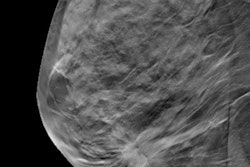

Mammography centers in the U.S. have rapidly adopted 3D mammography -- also known as digital breast tomosynthesis (DBT) -- despite the lack of large-scale clinical trials demonstrating the technology's value, according to an investigation by Kaiser Health News that was published in USA Today.

Interest in 3D mammography has prompted its swift implementation: Since its clearance by the U.S. Food and Drug Administration (FDA) in 2011, more than 63% of U.S. mammography facilities now offer the technology, according to the report. The exams add about $50 to the cost of a mammogram. When Medicare began to cover 3D mammography, the price increase added up to an additional $230 million on breast cancer screenings within the first three years, the author noted.